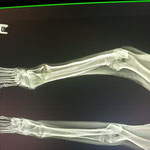

Tubbi a besoin de beaucoup d'amour et de contacts pour panser son doux cœur meurtri mais Tubbi aura sans doute aussi besoin de suivi et de soins pour sa dysplasie. Car ce brave chien a grandi très vite, sans doute mal nourri et surtout sans le moindre exercice. Son ossature s'est développée mais pas sa musculature. Il ne souffre pas car c'est un très jeune chien mais en prenant de l'âge des douleurs peuvent s'installer.